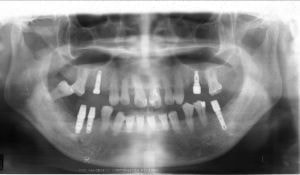

最近は、人工歯の適応症の拡大により天然歯+人工歯(インプラント補綴)にり、本来あるべき歯並びが再現できるようになり、高齢者の患者層が増えてきています。

治療例1 (インプラント補綴+矯正)